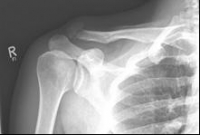

Acromioclavicular (lateral clavicular fracture), should be treated surgically, as a conservative therapy often leads to the formation of a so-called pseudarthrosis. Various implants are available, such as the hook plate and an anatomically preformed angular stable lateral clavicle plate.

Images: A lateral clavicle fracture was treated with a hook plate. The hook is fixed under the acromioclavicular, while screws anchor the plate in the collarbone.